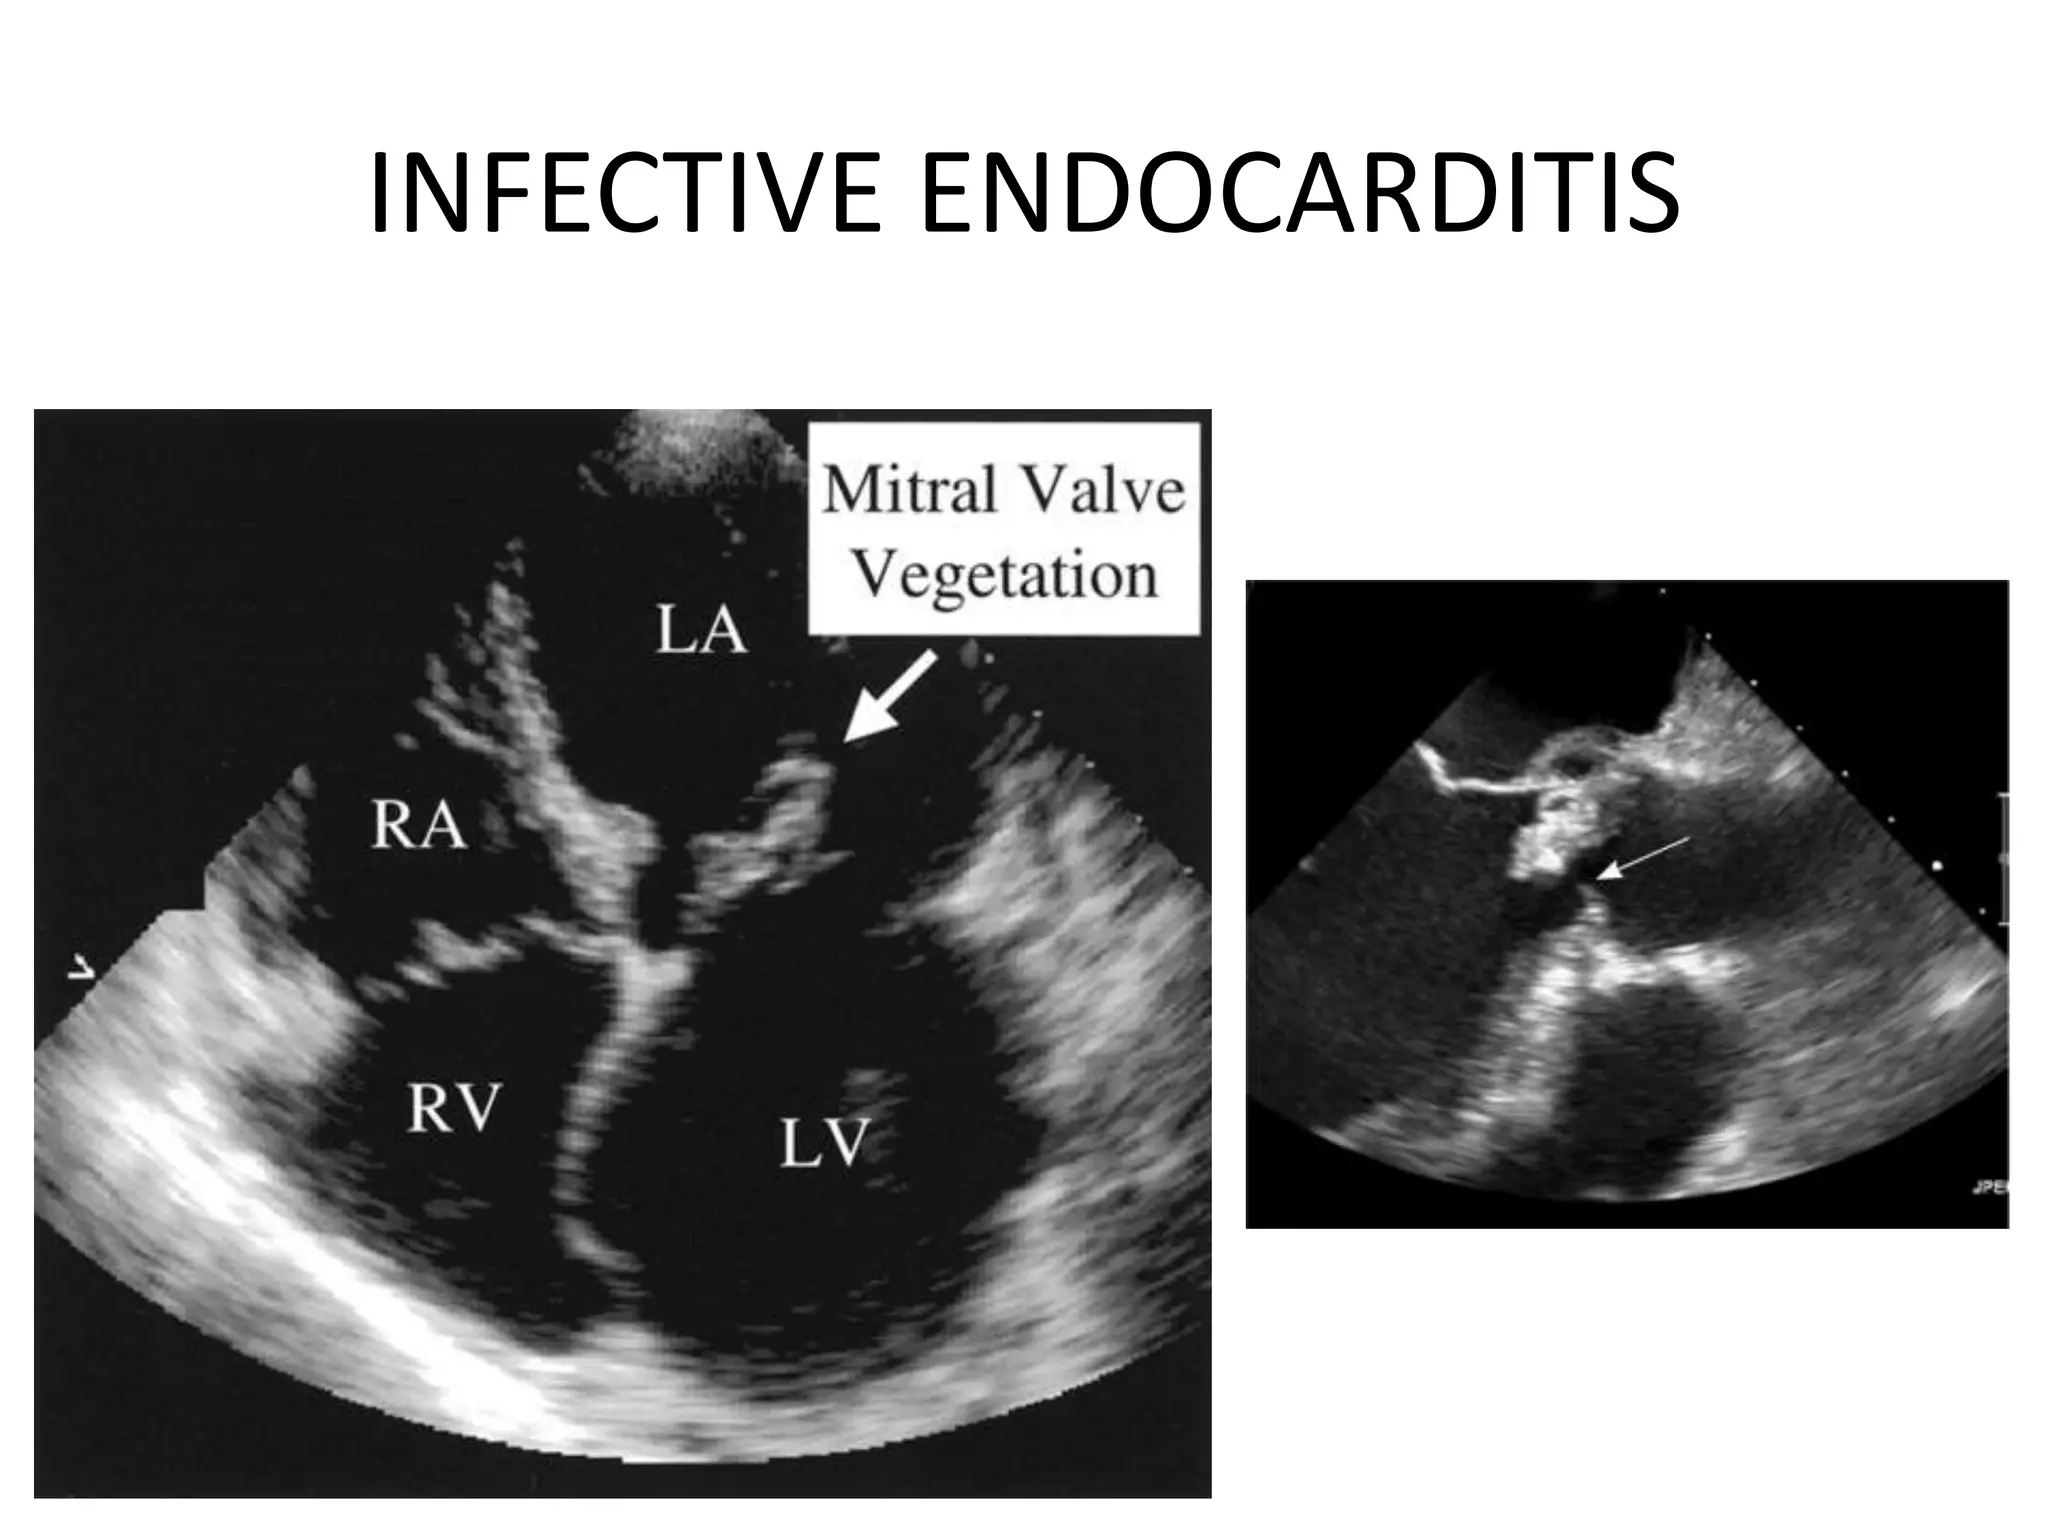

INFECTIVE ENDOCARDITIS